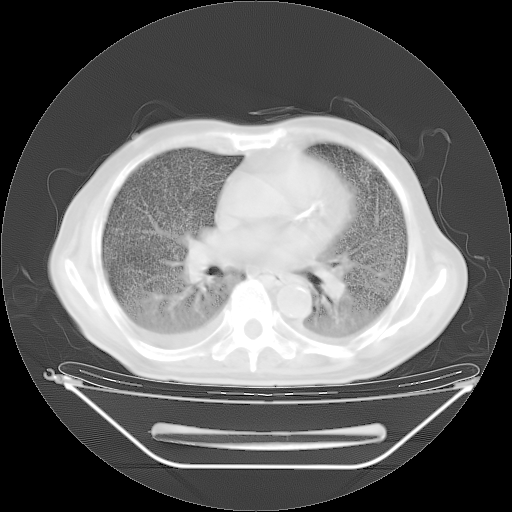

今天复查肺部CT,发现双肺广泛磨玻璃样改变。所以我把3月19日和5月9日相隔50天的肺部CT上传。请大家会诊。

5月9日肺部CT(在4月27日齐鲁医院肺部CT描述部分肺组织磨玻璃样改变,12天后肺组织广泛磨玻璃样改变)

大致读了系列胸部CT:纵隔窗无明显异常,肺窗:从4、27至今:主要是双肺中下野外带可见毛玻璃样改变,目前处于急性肺泡炎阶段,至于原因考虑1、结替组织或胶原血管性疾病所致?2、恶性疾病如恶组在肺部所致的表现或细支气管肺泡癌?3、药物或其它原因如肺蛋白沉着症所致肺泡炎目前不太可能?总之,明天就去请我院的呼吸科、感染科、血液科和临免专家会诊哈。